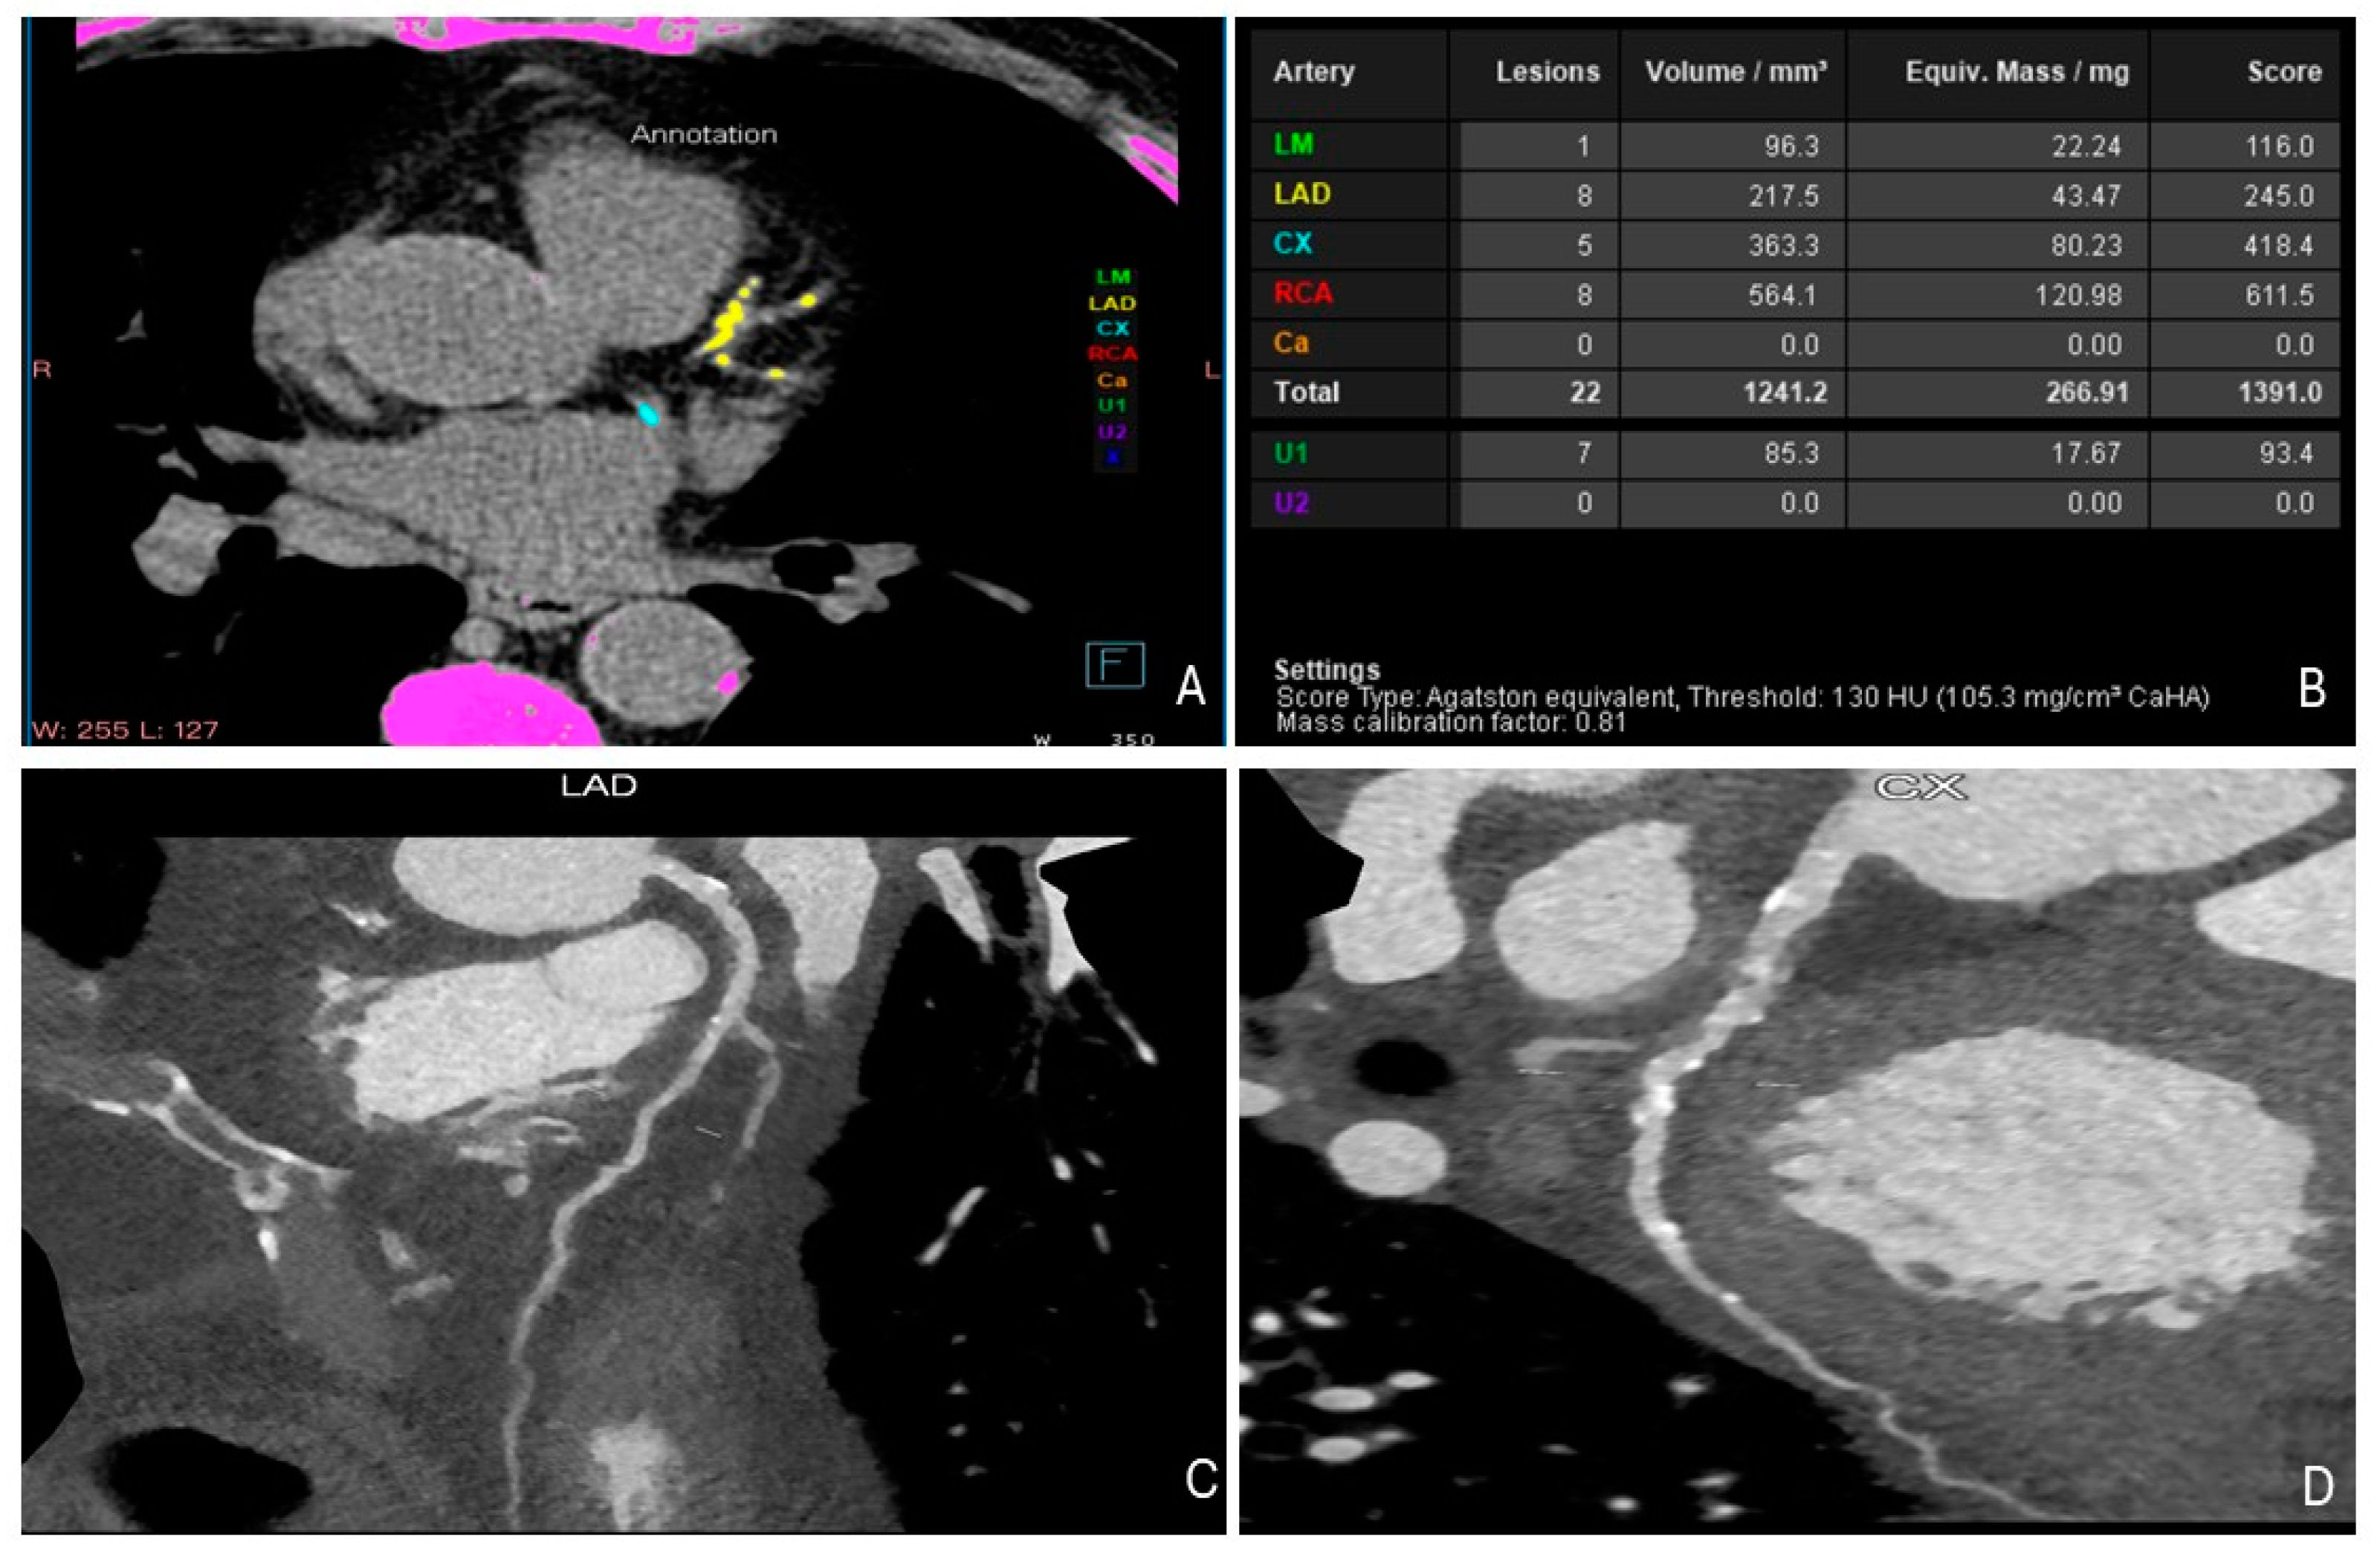

5. Cardiac Computed Tomography (CT)